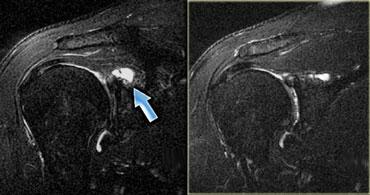

Hình bên trái là hình ảnh khảo sát cổ tay cho thấy một cơ gấp cẳng tay phụ.

Hình bên trái minh họa một cơ phụ ở mặt lưng cổ tay (trên chuỗi xung T1W và T2W).

Dưới vị trí đánh dấu là một khối bờ rõ, đồng tín hiệu với cơ bình thường.

Đây là một cơ ở mức giữa các xương cổ tay, có tín hiệu bình thường.

Thông thường, ở mức này, không có cơ nào ở phía duỗi của cổ tay, chỉ có gân.

Đây là cơ duỗi ngón tay ngắn phụ (accessory extensor digitorum manus brevis).